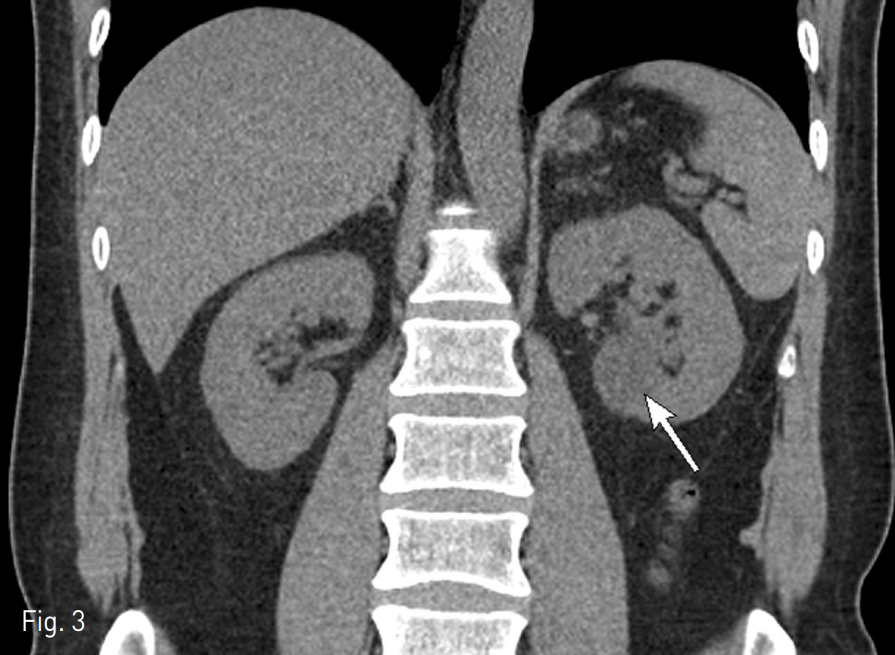

시술 직후 환자는 즉각적으로 통증이 호전되었고 2개월 후에 촬영한 복부 CT상 좌측 단순신장낭종의 크기는 2.7cm으로 크기가 줄어들었으며 수신증도 소실되었고 더 이상의 통증을 호소하지 않았다 (Fig. 3).

Fig. 3

2-month follow-up abdominal non-enhanced coronal CT scan shows no more hydronephrosis and decreased size of the simple renal cyst (arrow).